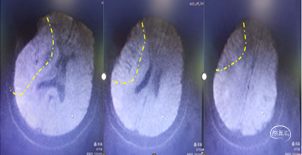

裸奔抽吸:通过导引导管将中间导管0.070-125cm置于颈内动脉起始部,"裸奔"边抽吸边上,抽吸3次,到达C4段,但以远血管仍不通畅。

导丝导引下抽吸:微导丝携带微导管,在中间导管支撑下到达C6-M1起始部,中间导管再次边抽吸边上至M1起始部,抽出部分血栓,中间导管造影示大脑前通畅,大脑中动脉仍不通。

支架取栓联合抽吸:再次将微导丝偿试通过M1段,到达大脑中动脉分叉部分,跟进微导管至分叉部,通过微导管释放4ⅹ20mm取栓支架,静置5分钟,向前跟进微导管,收拢支架,跟进中间导管至M1。边抽拉微导管和支架负压抽吸下将支架拉入中间导管内撤出体外,抽出大量黯红色血栓,支架内抓出黯黑色血栓。

中间导管内造影示大脑中动脉上干、下干通畅,远端血流良好,但上干、下干分叉后血管内仍有发白,考虑仍有血栓或斑块。

再次取栓:再次将支架置于M2段上干,释放支架,跟进中间导管至M1分叉近端,再次取栓和抽吸,取出少量血栓。